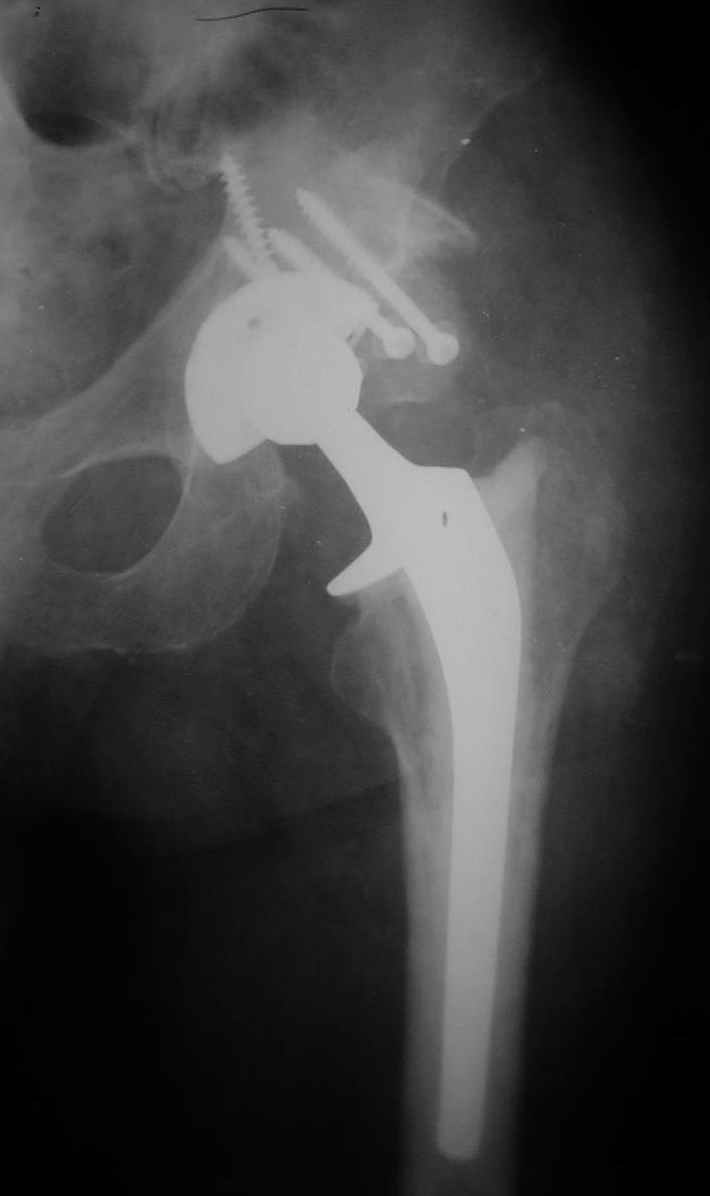

РАВ> Есть ли у Вас примеры установки протеза при обширных дефектах впадины?

РАВ> Какой был самый большой дефицит задней колонны, какой срок наблюдения,

РАВ> довольны ли Вы результатом?

Максимальные сроки наблюдения 5-6 лет. С появлением современных эндопротезов результаты сравнимы с первичным протезированием при обычном КА. Но, каждая операция нестандартная и требуется

тщательнейшее планирование каждого шага и необходимо иметь несколько запасных вариантов.

Схематично можно сказать так - если есть контакт с 60% и более ВВ, то этого достаточно для последующей биологической фиксации чашки. Опять же НО, мы стараемся "подрыться" фрезами так, что бы был приемлимый упор чашки, а фиксация аутотрансплантата головки была прочной без каких либо дефектов и зазоров.

Если у Вас есть дефект крыши, то никакая пластика не выдержит, лучше сразу ставить опорные кольца, все зависит от локализации костного дефекта.

В институте совместно с фирмой Зиммер достаточно регулярно (практически ежемесячно) проводятся 2-х недельные циклы по различным вопросам эндопротезирования. Если есть возможность и желание, мы готовы поделиться с Вами нашим опытом, тем более есть что показать и что обсудить - в настоящее время ежедневно выполняется от 6 до 10 эндопротезирований коленного и тазобедренного сустава. В качестве примеров хочу показать 2 наблюдения, через 1 год и 5 лет после операции

5 лет